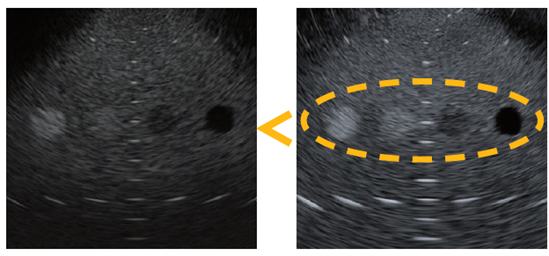

超音波の送受信処理の高精度化により、従来品と比較して画質の大幅な向上を実現しました。病変の有無や内部の性状などをより鮮明に描出し、信頼性の高い診断・治療方針の決定をサポートします。

▲左:従来機種、 右:EU-ME3